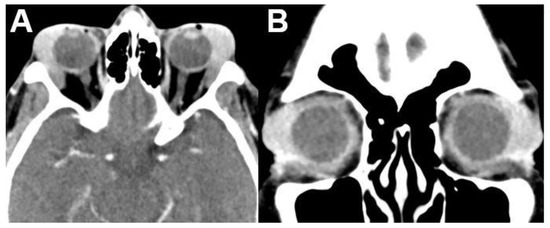

3.1.1. Retinoblastoma